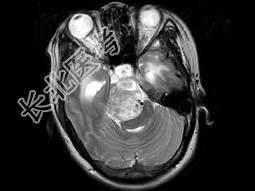

- 单项选择题女,32岁, 头痛、右侧肢体功能障碍约1年,声音嘶哑, 饮水呛咳,根据所提供图像, 最可能的诊断是 ( )

A、(斜坡)脑膜瘤

B、(斜坡)脊索瘤

C、(斜坡)神经鞘瘤

D、(斜坡)软骨瘤

E、(斜坡)海绵状血管瘤